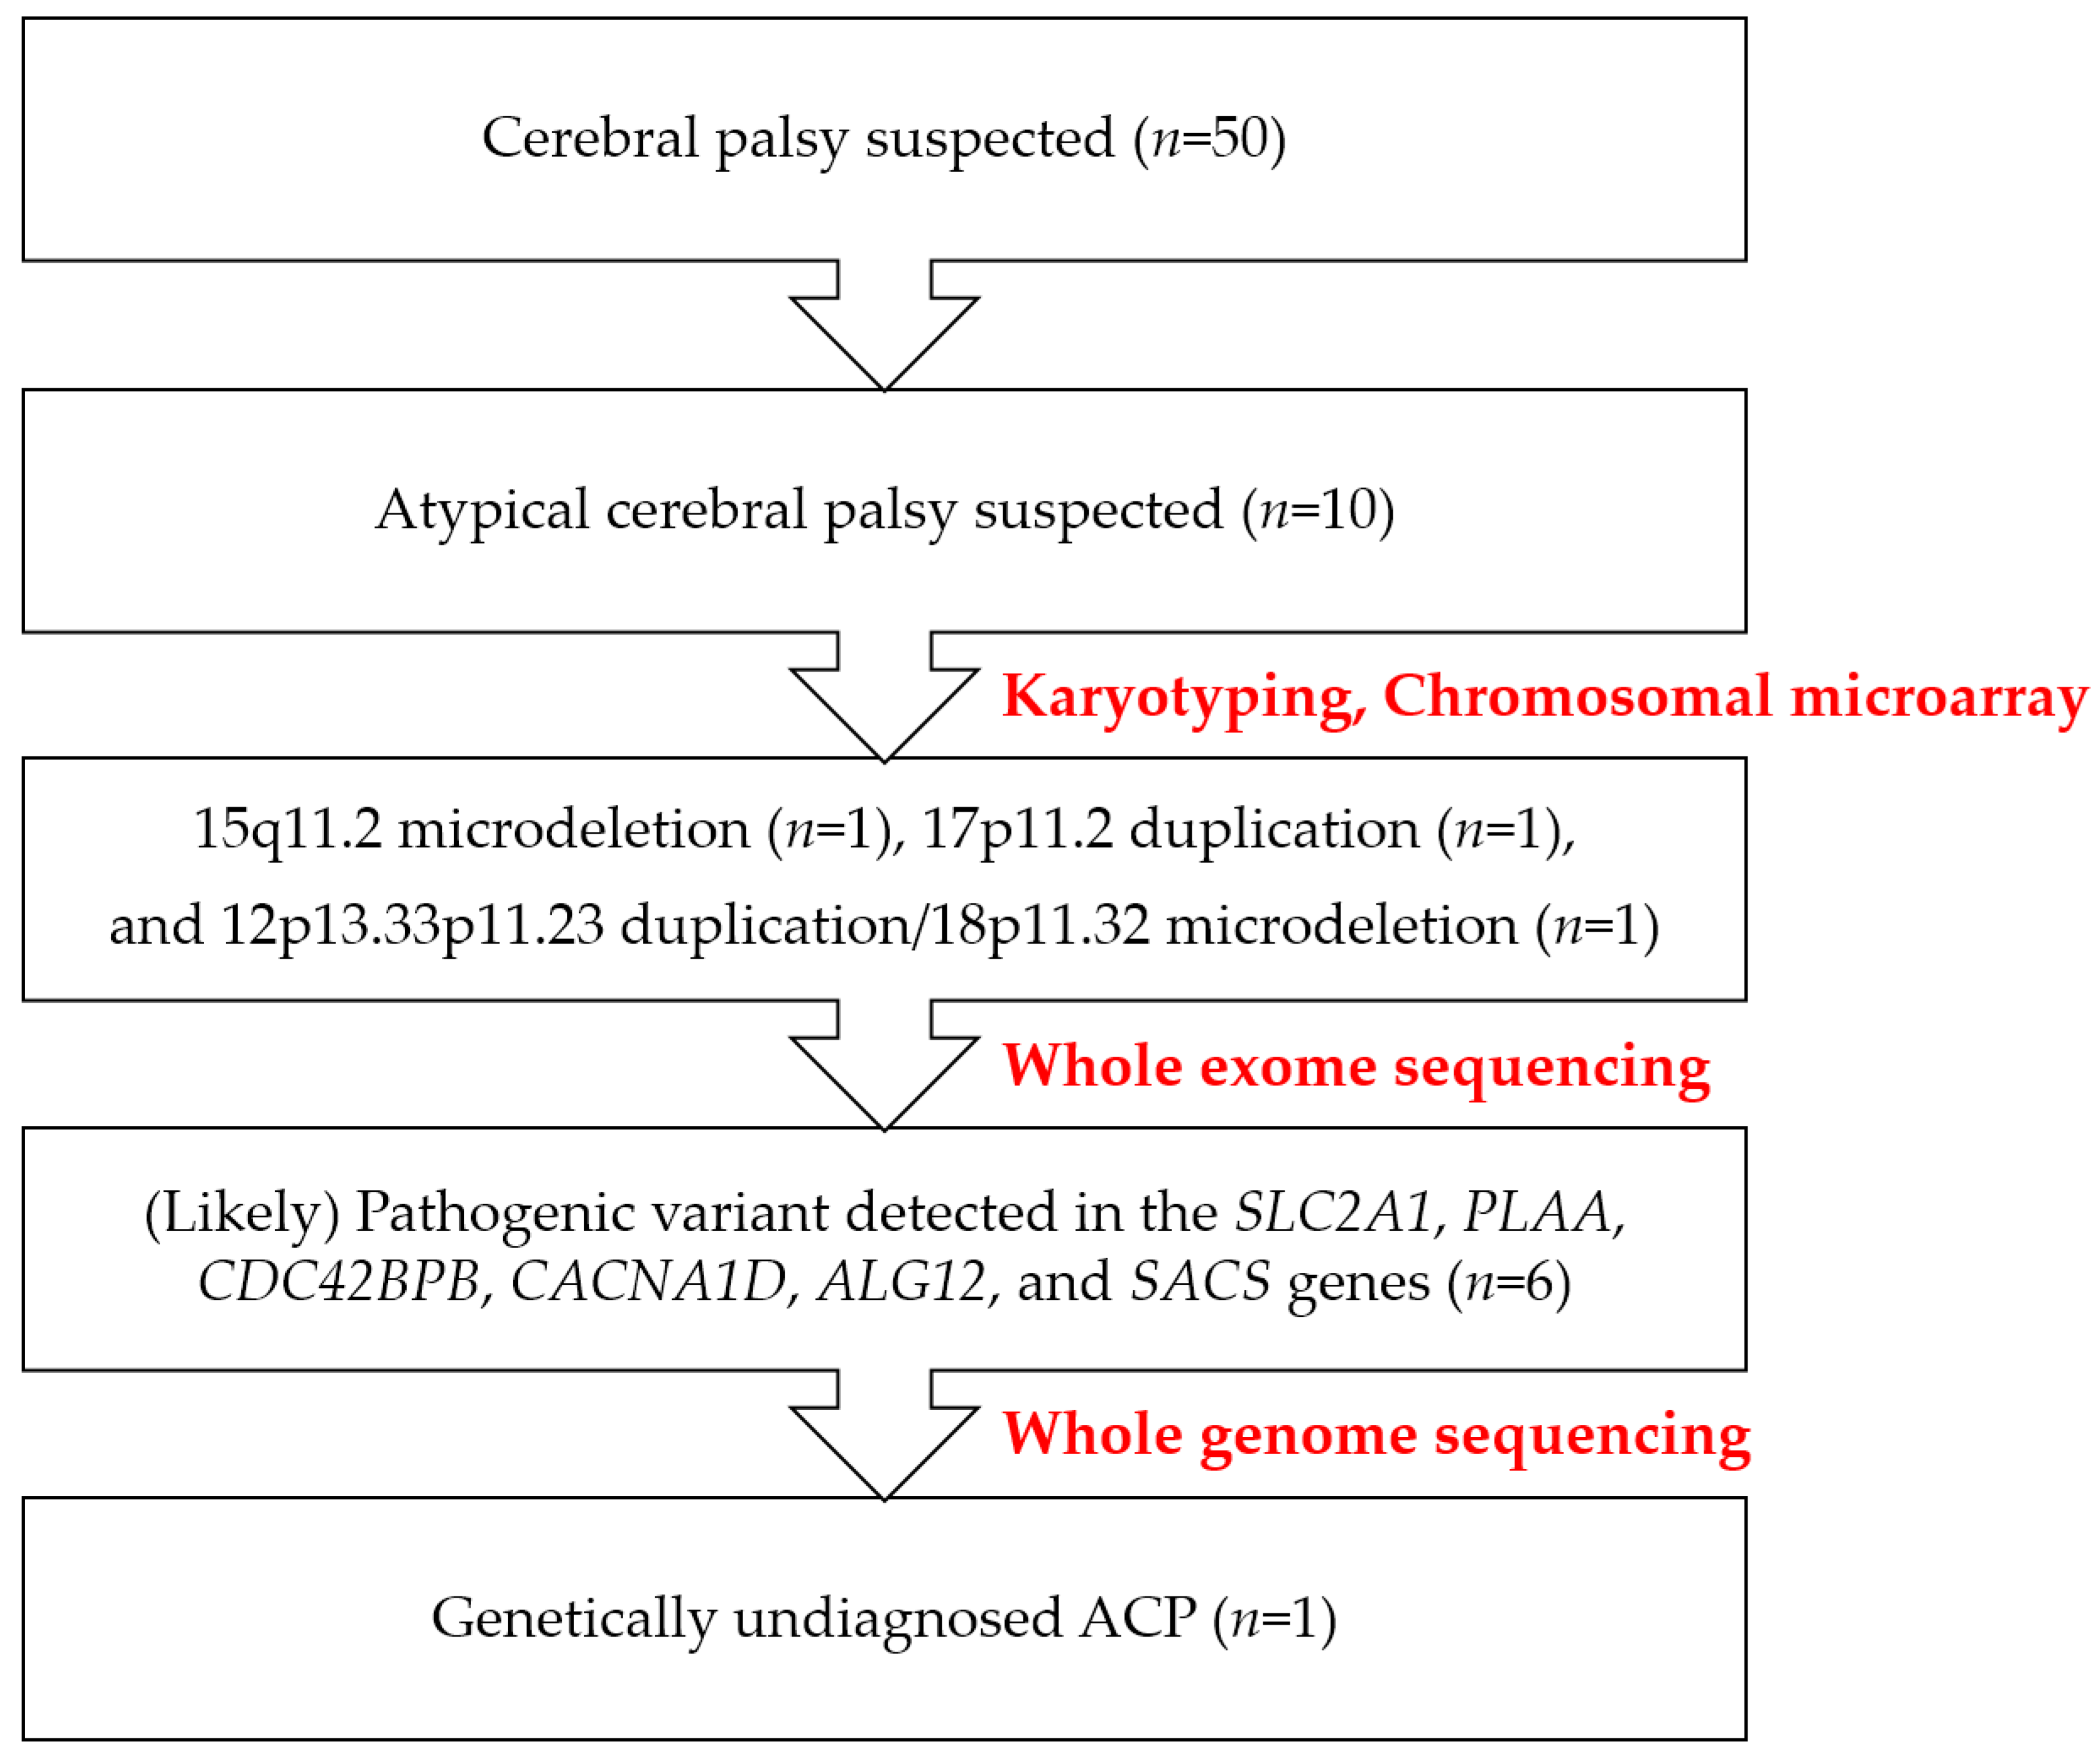

2. Results

2.1. Presentation of a Genetically Diagnosed Case Series in Atypical Cerebral Palsy

4. Materials and Methods

4.1. Patients

4.2. Single Nucleotide Polymorphism (SNP) Microarray and Data Interpretation

4.3. Library Preparation, Exome Sequencing, Genome Sequencing, and Bioinformatic Analysis